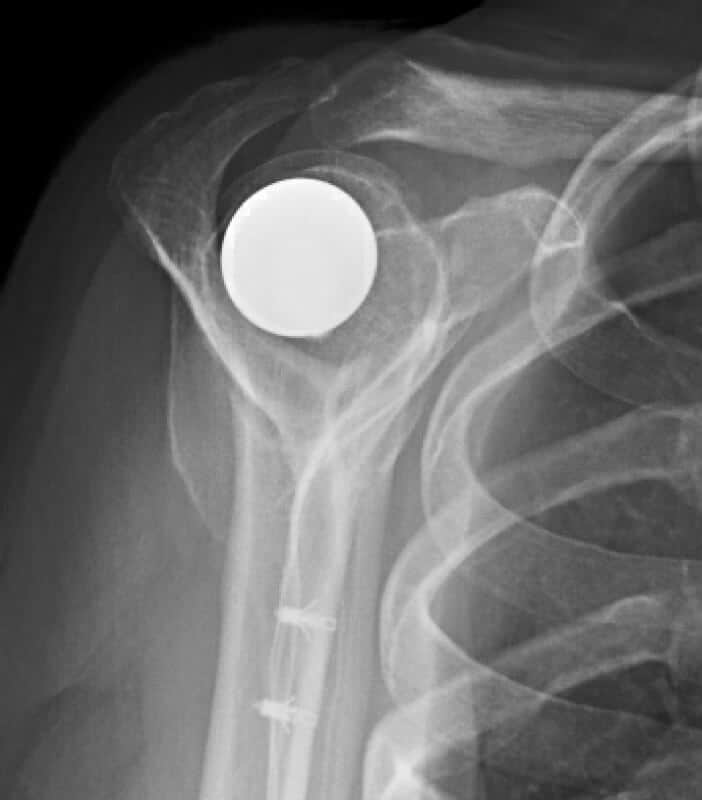

Arthrosurface, HemiCap Small